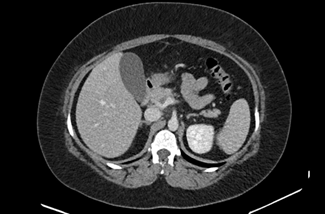

The initial physical examination showed a patient in discomfort but with normal vital signs. The abdominal palpation revealed epigastric tenderness without guarding or without other signs suggestive of acute abdomen. Surgical sites appeared to be well-healed, clean, and dry with no evidence of drainage or dehiscence. The laboratory analyses showed elevated inflammatory parameters (13,500 leukocytes and a C-reactive protein level of 123,20 mg/dL) and normal levels of amylase and lipase. A contrast-enhanced abdominopelvic computed tomography (CT) scan (Figures 1, 2, and 3) showed a dilatation in the mesenteric vessels, particularly the superior mesenteric vein, which had a luminal filling defect near its confluence with the splenic vein. The CT scan also revealed thickening of the adjacent adipose tissue, albeit without signs of intestinal ischemia. The patient was admitted to ward and started on LMWH 100 mg every 12 hours along with reinforced IV hydration. After three days in the hospital, she was discharge home asymptomatic. Anticoagulation therapy was continued with LMWH for one month before transitioning to a non-vitamin K antagonist oral anticoagulant (NOAC), specifically Apixaban 5 mg every 12 hours, and the use of estrogen for birth control was discontinued. At the three-month follow-up, the patient had lost 20 kg and was scheduled to repeat the CT scan and to discontinue anticoagulation therapy approximately six months after the thrombotic event.

The most common presentation of PMVT is nonspecific, often characterized by a diffuse abdominal pain, accompanied by nausea, vomiting, and changes in bowel habits.12 Enhanced abdominal CT with intravenous contrast, is the gold standard method for diagnosing PMVT, boasting a high sensitivity of 90%. (10) In the CT scan, we can identify the affected vascular territory and determine if there is intestinal compromise. The presence of free fluid, pneumoperitoneum, or indirect signs of intestinal ischemia (non-enhancing or hypo-enhancing bowel wall after contrast injection, pneumatosis intestinalis, portomesenteric venous gas and alteration in wall thickness) are warning signs that should prompt urgent surgery.13